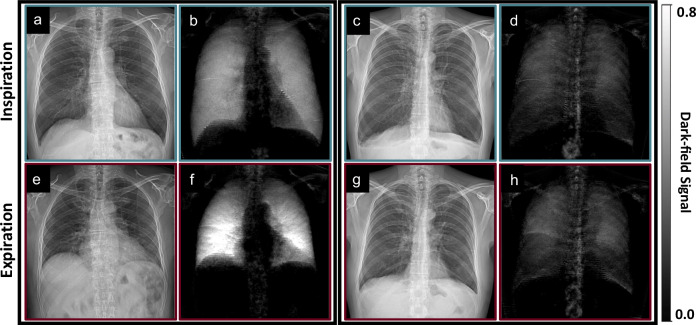

健康和肺气肿患者吸气和呼气的暗场胸片信号特征。

背景:暗场胸片对肺泡结构敏感。我们评估了吸气和呼气时暗场信号的变化。方法:前瞻性纳入2018 - 2020年行胸部计算机断层扫描(CT)的患者,不包括CT上可见的肺气肿以外的任何肺部疾病。参与者在吸气和呼气时使用原型暗场胸部x线摄影系统进行成像。我们计算了总暗场信号∑DF和暗场系数λ,假设它们分别与肺泡总数和肺泡密度成正比。结果:入组88例,年龄64岁±11岁(平均±标准差),男性55例。呼气时肺投影暗场信号明显高于吸气时。在所有参与者中,∑DF吸气(1.6 × 10-2±0.4 × 10-2 m2)高于呼气(1.5 × 10-2±0.4 m2) (p -1)高于呼气(3.1±1.1 m-1)(中度肺气肿呼气时p -1,而无肺气肿呼气时∑DF = 3.6±0.7 m-1 (p = 0.003)。结论:暗场信号与呼吸状态有关。呼吸状态的差异受肺气肿严重程度的影响。相关性声明:患者的呼吸状态影响暗场胸片,可能影响其诊断价值。重点:暗场胸片吸气与呼气变化的信号特征。从吸气到呼气,总暗场信号略有减小,而暗场系数则显著增大。呼气与吸气总暗场信号之比与肺气肿严重程度无关,而暗场系数之比与肺气肿严重程度有关。

Background: Dark-field chest radiography is sensitive to the lung alveolar structure. We evaluated the change of dark-field signal between inspiration and expiration.

Methods: From 2018 to 2020, patients who underwent chest computed tomography (CT) were prospectively enrolled, excluding those with any lung condition besides emphysema visible on CT. Participants were imaged in both inspiration and expiration with a prototype dark-field chest radiography system. We calculated the total dark-field signal ∑DF and the dark-field coefficient ϵ, assumed to be proportional to the total number of alveoli and the alveolar density, respectively.

Results: Eighty-eight subjects, aged 64 years ± 11 (mean ± standard deviation), 55 males, were enrolled. Dark-field signal in the lung projection appeared higher in expiration compared to inspiration. Over all participants, ∑DF was higher in inspiration (1.6 × 10-2 ± 0.4 × 10-2 m2) compared to expiration (1.5 × 10-2 ± 0.4 m2) (p < 0.001), with its expiration-to-inspiration not ratio being different for any emphysema subgroup. The dark-field coefficient ϵ was lower in inspiration (2.3 ± 0.6 m-1) compared to expiration (3.1 ± 1.1 m-1) (p < 0.001) over all participants. The dark-field coefficient in inspiration and expiration, as well as their ratio, was lower for at least moderate emphysema when compared to the control group (e.g., ϵ = 2.5 ± 1.0 m-1 for moderate emphysema in expiration versus ϵ = 3.6 ± 0.7 m-1 for participants without emphysema (p = 0.003).

Conclusion: The dark-field signal depends on the breathing state. Differences between breathing states are influenced by emphysema severity.

Relevance statement: The patient's breathing state influences the dark-field chest radiograph, potentially impacting its diagnostic value.

Key points: Signal characteristics in dark-field chest radiography change between inspiration and expiration. The total dark-field signal decreases slightly from inspiration to expiration, while the dark-field coefficient increases substantially. The ratio of the total dark-field signal between expiration and inspiration is independent of emphysema severity, whereas the ratio of the dark-field coefficient depends on emphysema severity.